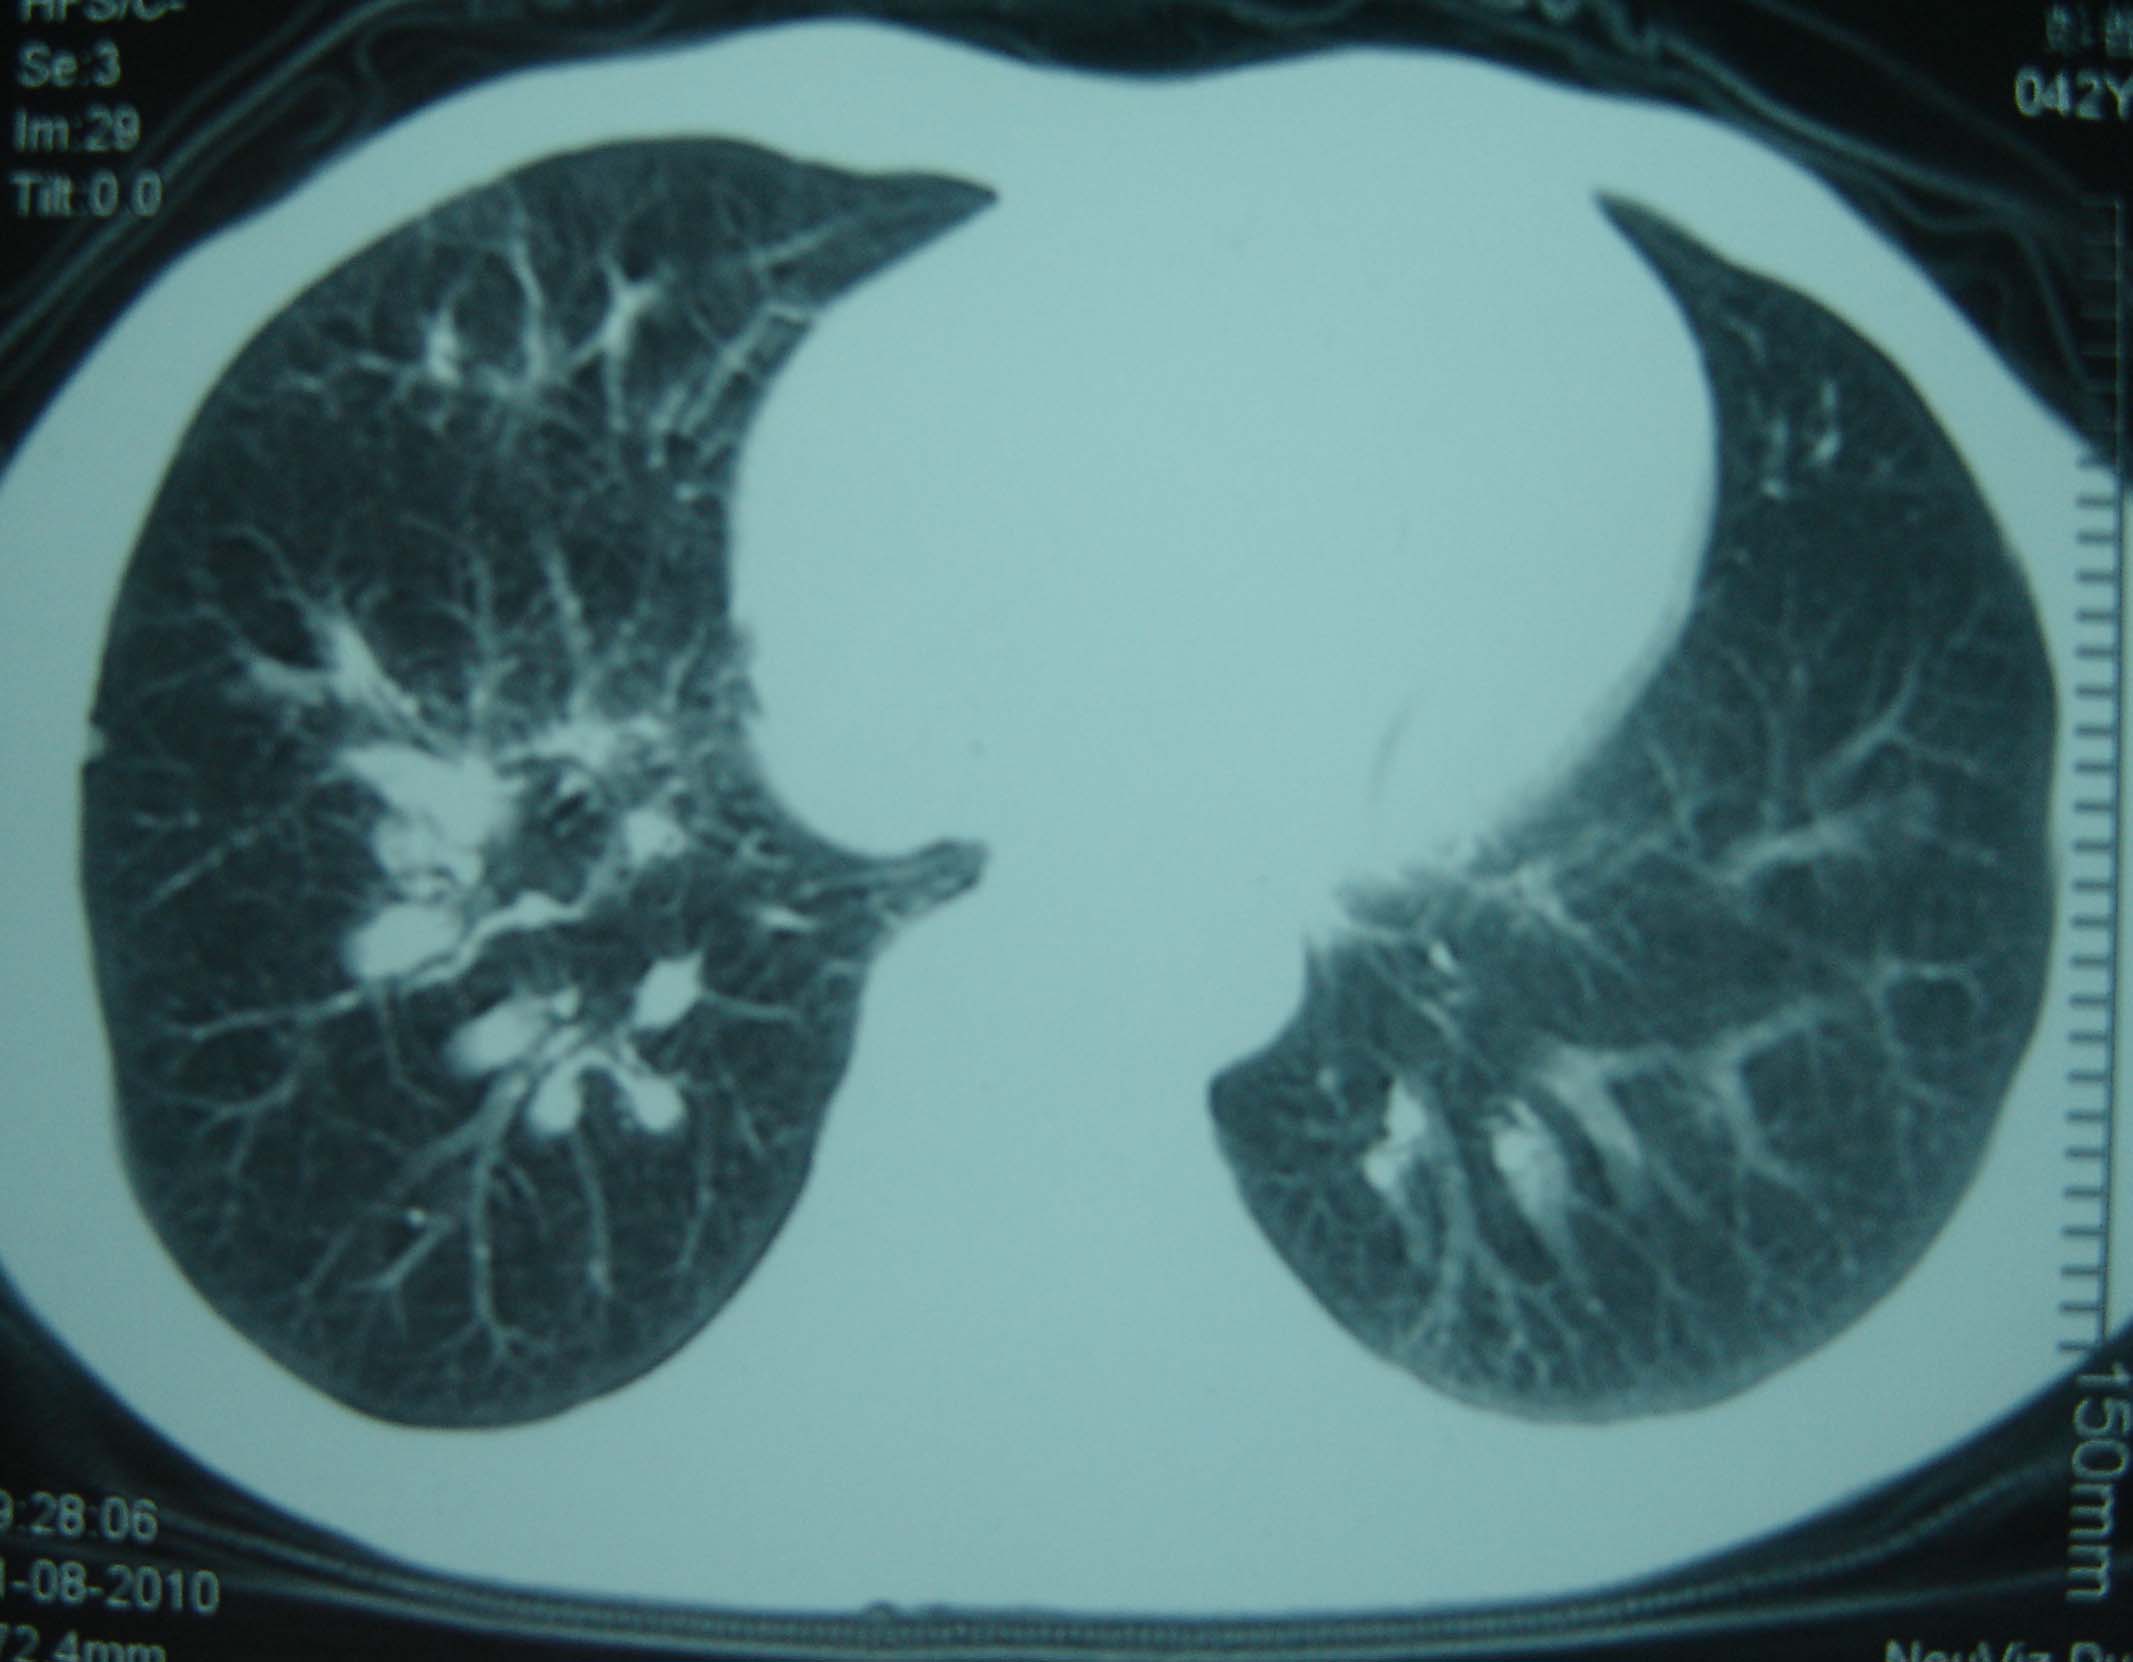

标题: CT25321:两肺多发结节 请会诊 [打印本页]

标题: CT25321:两肺多发结节 请会诊

男 、43岁,咳嗽胸痛,装修工,平时接触粉尘较多,有吸烟史10多年,纤维支气管镜检查未发现异常,胃镜、腹部b超检查亦未发现异常,颈部淋巴结活检未发现肿瘤细胞。

不能排除转移,如果不能找到原发灶,只有短期随访。

结节病?转移瘤?

结节病。

转移瘤?

1)考虑双肺及胸膜多发性转移瘤。2)肺气肿。

双肺结节病。